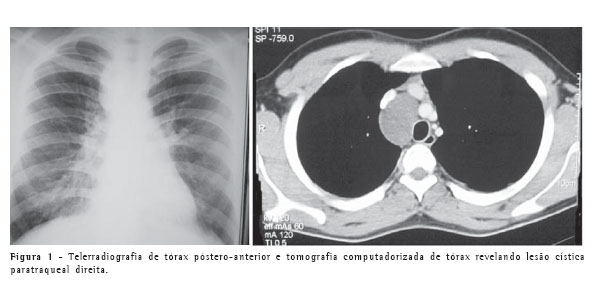

Um paciente de 22 anos, do sexo masculino, procurou atendimento médico devido a tosse seca persistente. Negava quaisquer outros sintomas. Realizou telerradiografia de tórax que evidenciou alargamento mediastinal na região paratraqueal direita. Foi então submetido à tomografia computadorizada do tórax (Figura 1), que mostrou a presença de lesão cística paratraqueal direita, com 6 cm de diâmetro, deslocando a veia cava superior anteriormente e a traquéia para a esquerda. O exame físico era normal e o paciente não apresentava co-morbidades.